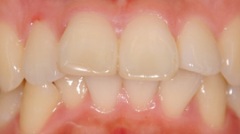

審美的治療の実例

出っ 歯が気になって来院した患者様です。海外に行くことが決まっていたので、矯正治療をするだけの時間の余裕がありませんでした。そこで、上の前歯4本をオー ルセラミッククラウンに変えました。いかがですか?どれが人口の歯か見分けがつきません。患者様ご本人も大満足してくださいました。

当院では咬み合わせ、歯列のみならず、歯肉との調和も考慮し治療にあたります。自然さを追求し、治療した後も結果を長く安定させるように、しっかりとメインテナンスサポート致します。

| Before | After |